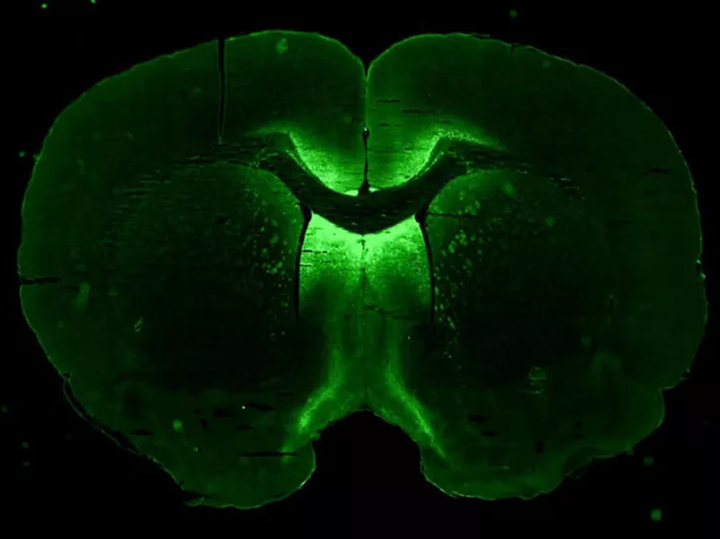

Трехмерная структура, которая была получена учеными в лаборатории из клеток мозга. Светящиеся зеленые клетки — это нейроны. Изображение предоставлено NASA Axonis Therapeutics, Inc.

На станции их попробуют «направить» на формирование нейронов для пересыла электрических и химических сигналов в мозг, а также на создание еще двух типов клеток мозга – микроглию и астроциты. В задачи дополнительных клеток входит поддержание контактов между нервными клетками и защита мозга от инфекций.

Предполагается, что все три типа клеток будут «собираться» воедино, формируя небольшие сферы – «сфероиды», которые можно использовать для моделирования заболеваний головного мозга человека и для тестирования лекарств.